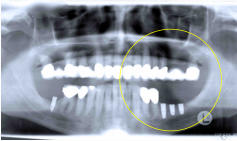

Nach

entsprechender

Vorbereitung

-

ggf.

Knochenneuaufbau

eines

bereits

geschwächten

Kieferkamms

werden

die

Implantate

in

den

Kieferknochen

eingesetzt.

einer

Einheilzeit

von

3

bis

6

Monaten,

der

Mikrostrukturen

des

Implantats

einwächst,

kann

das

Implantat

belastet

und

geplante

Zahnersatz

angefertigt

auf

ihm

befestigt werden.